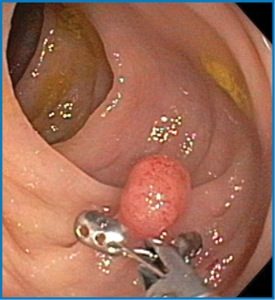

Κολονοσκόπηση: Μια διαδικασία κατά την οποία ένας μακρύς, λεπτός, εύκαμπτος σωλήνας τοποθετείται από τον πρωκτό μέσα στο παχύ έντερο. Ο σωλήνας διαθέτει μια κάμερα που δείχνει εικόνες σε μια οθόνη και ένα εργαλείο για να κόψει τυχόν πολύποδες.

Όταν εντοπιστεί ένας πολύποδας, ο γιατρός θα το αφαιρέσει και θα το εξετάσει για να δει τι είδους είναι. Οι περισσότεροι πολύποδες αφαιρούνται κατά τη διάρκεια μιας κολονοσκόπησης. Ο γιατρός σας θα καθορίσει πότε θα πρέπει να πραγματοποιήσετε μια επανάληψη της εξέτασης ελέγχου βάσει του αριθμού των πολύποδων, του τύπου των πολύποδων και των παραγόντων κινδύνου.